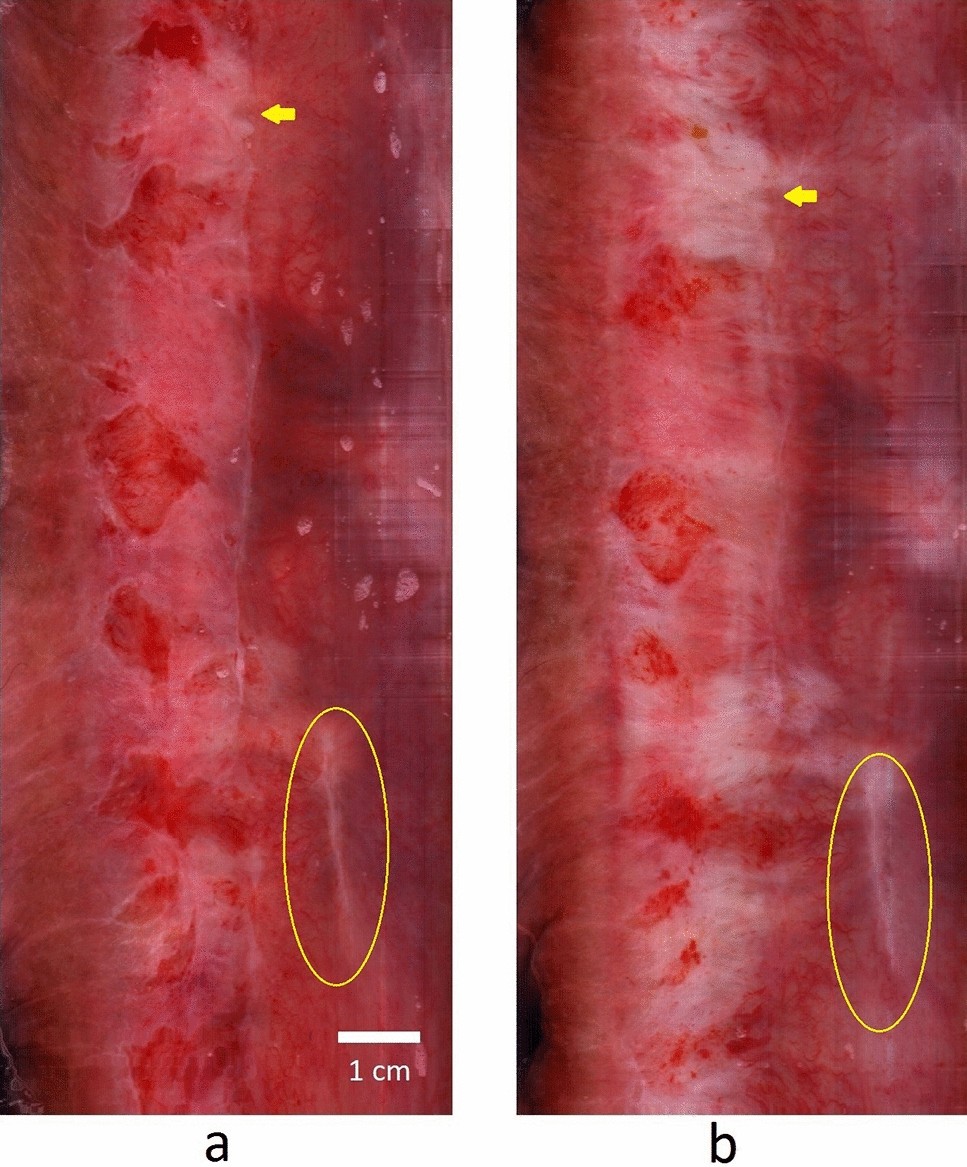

Figure 2

Serial images demonstrate acetic acid induced changes in the anal canal epithelium. The wide field-of-view (FOV) image of the anal canal (a) pre-acetic acid and (b) post-acetic acid. The increased whiteness (arrow) is the noted effect of acetic acid instillation. The yellow circle identifies a surgical scar in the pre-acetic acid and in the post-acetic acid images.